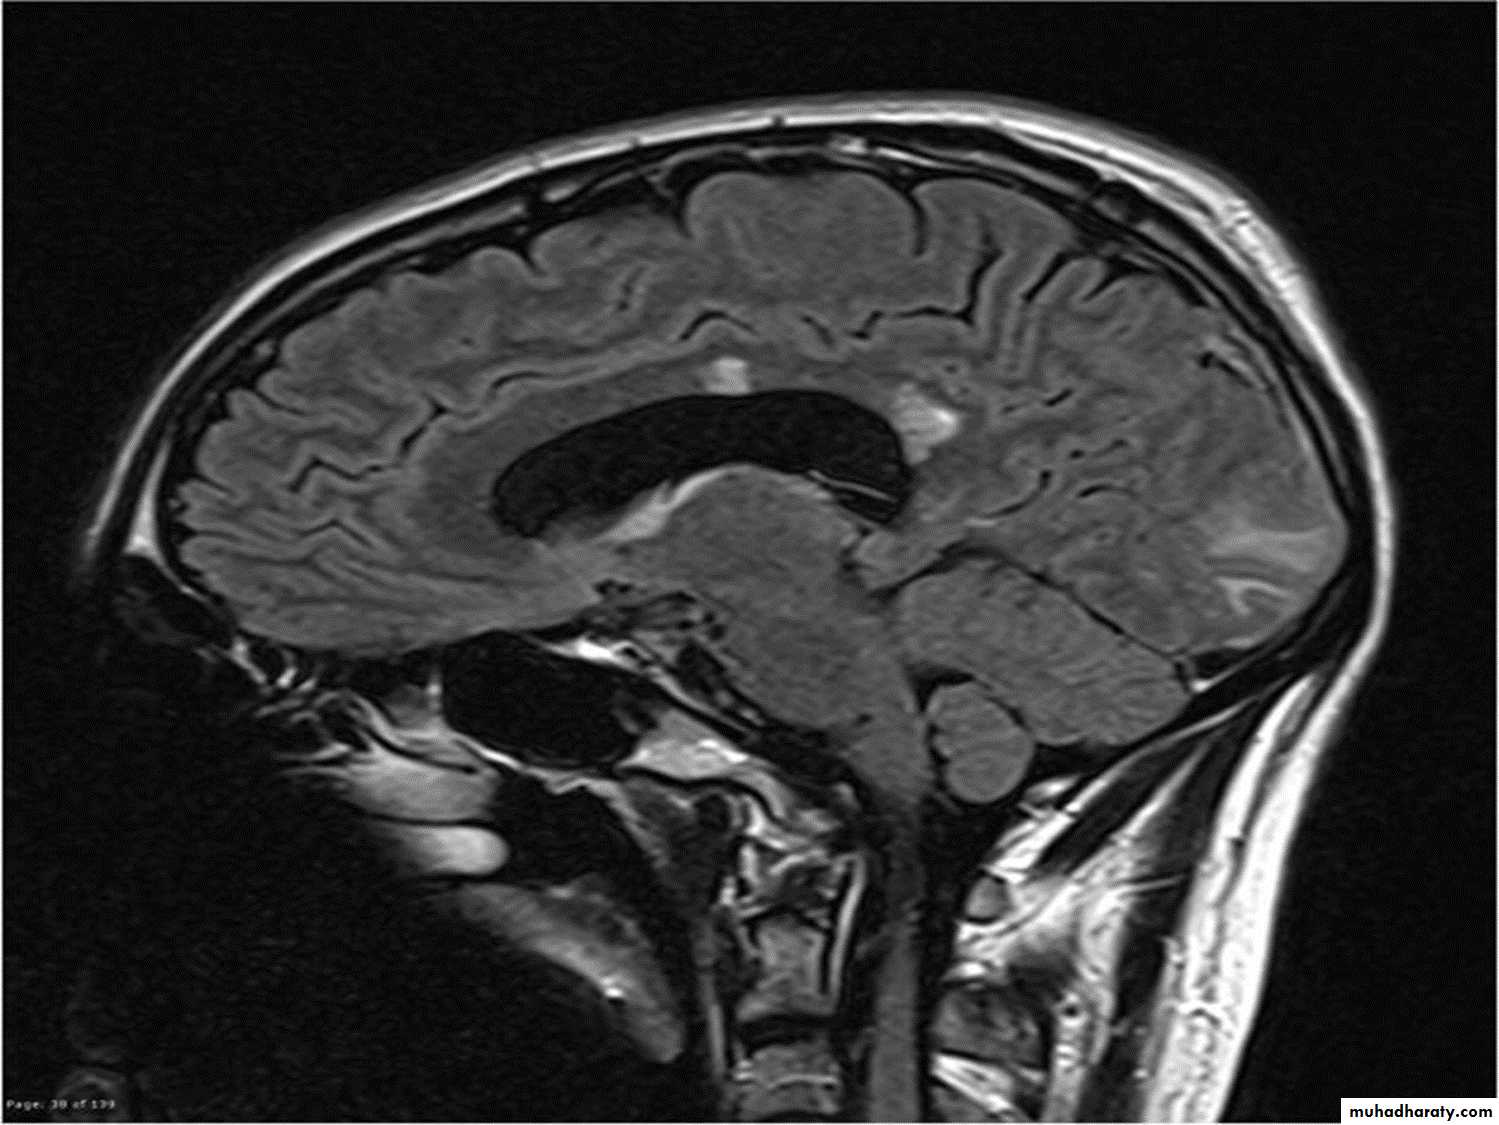

Lesions are frequently oriented perpendicular to the ventricular surface,(Dawson’s fingers)

Lesions larger than 6 mm located in the corpus callosum, periventricular white matter, brainstem, cerebellum, or spinal cord are particularly helpful diagnostically

The brain MRI was classically thought to be normal at the onset of NMO